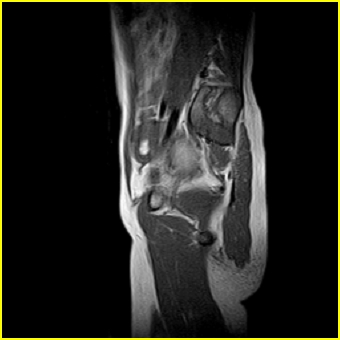

女、15岁、下腹疼痛2天,排尿困难1天。查体:处女膜闭锁,距处女膜约4至5cm处扪及一约5cm直径的圆形包块,张力较高,触痛明显、欠活动。b超提示子宫增大伴宫内增强回声团。

影像意见:子宫直肠陷凹积血。

更正影像意见:阴道积血。

处女膜闭锁,阴道积血

处女膜闭锁,阴道积血,子宫积血.

阴道积血,子宫积血.

子宫及阴道积血。

处女膜闭锁,伴子宫及阴道积血.